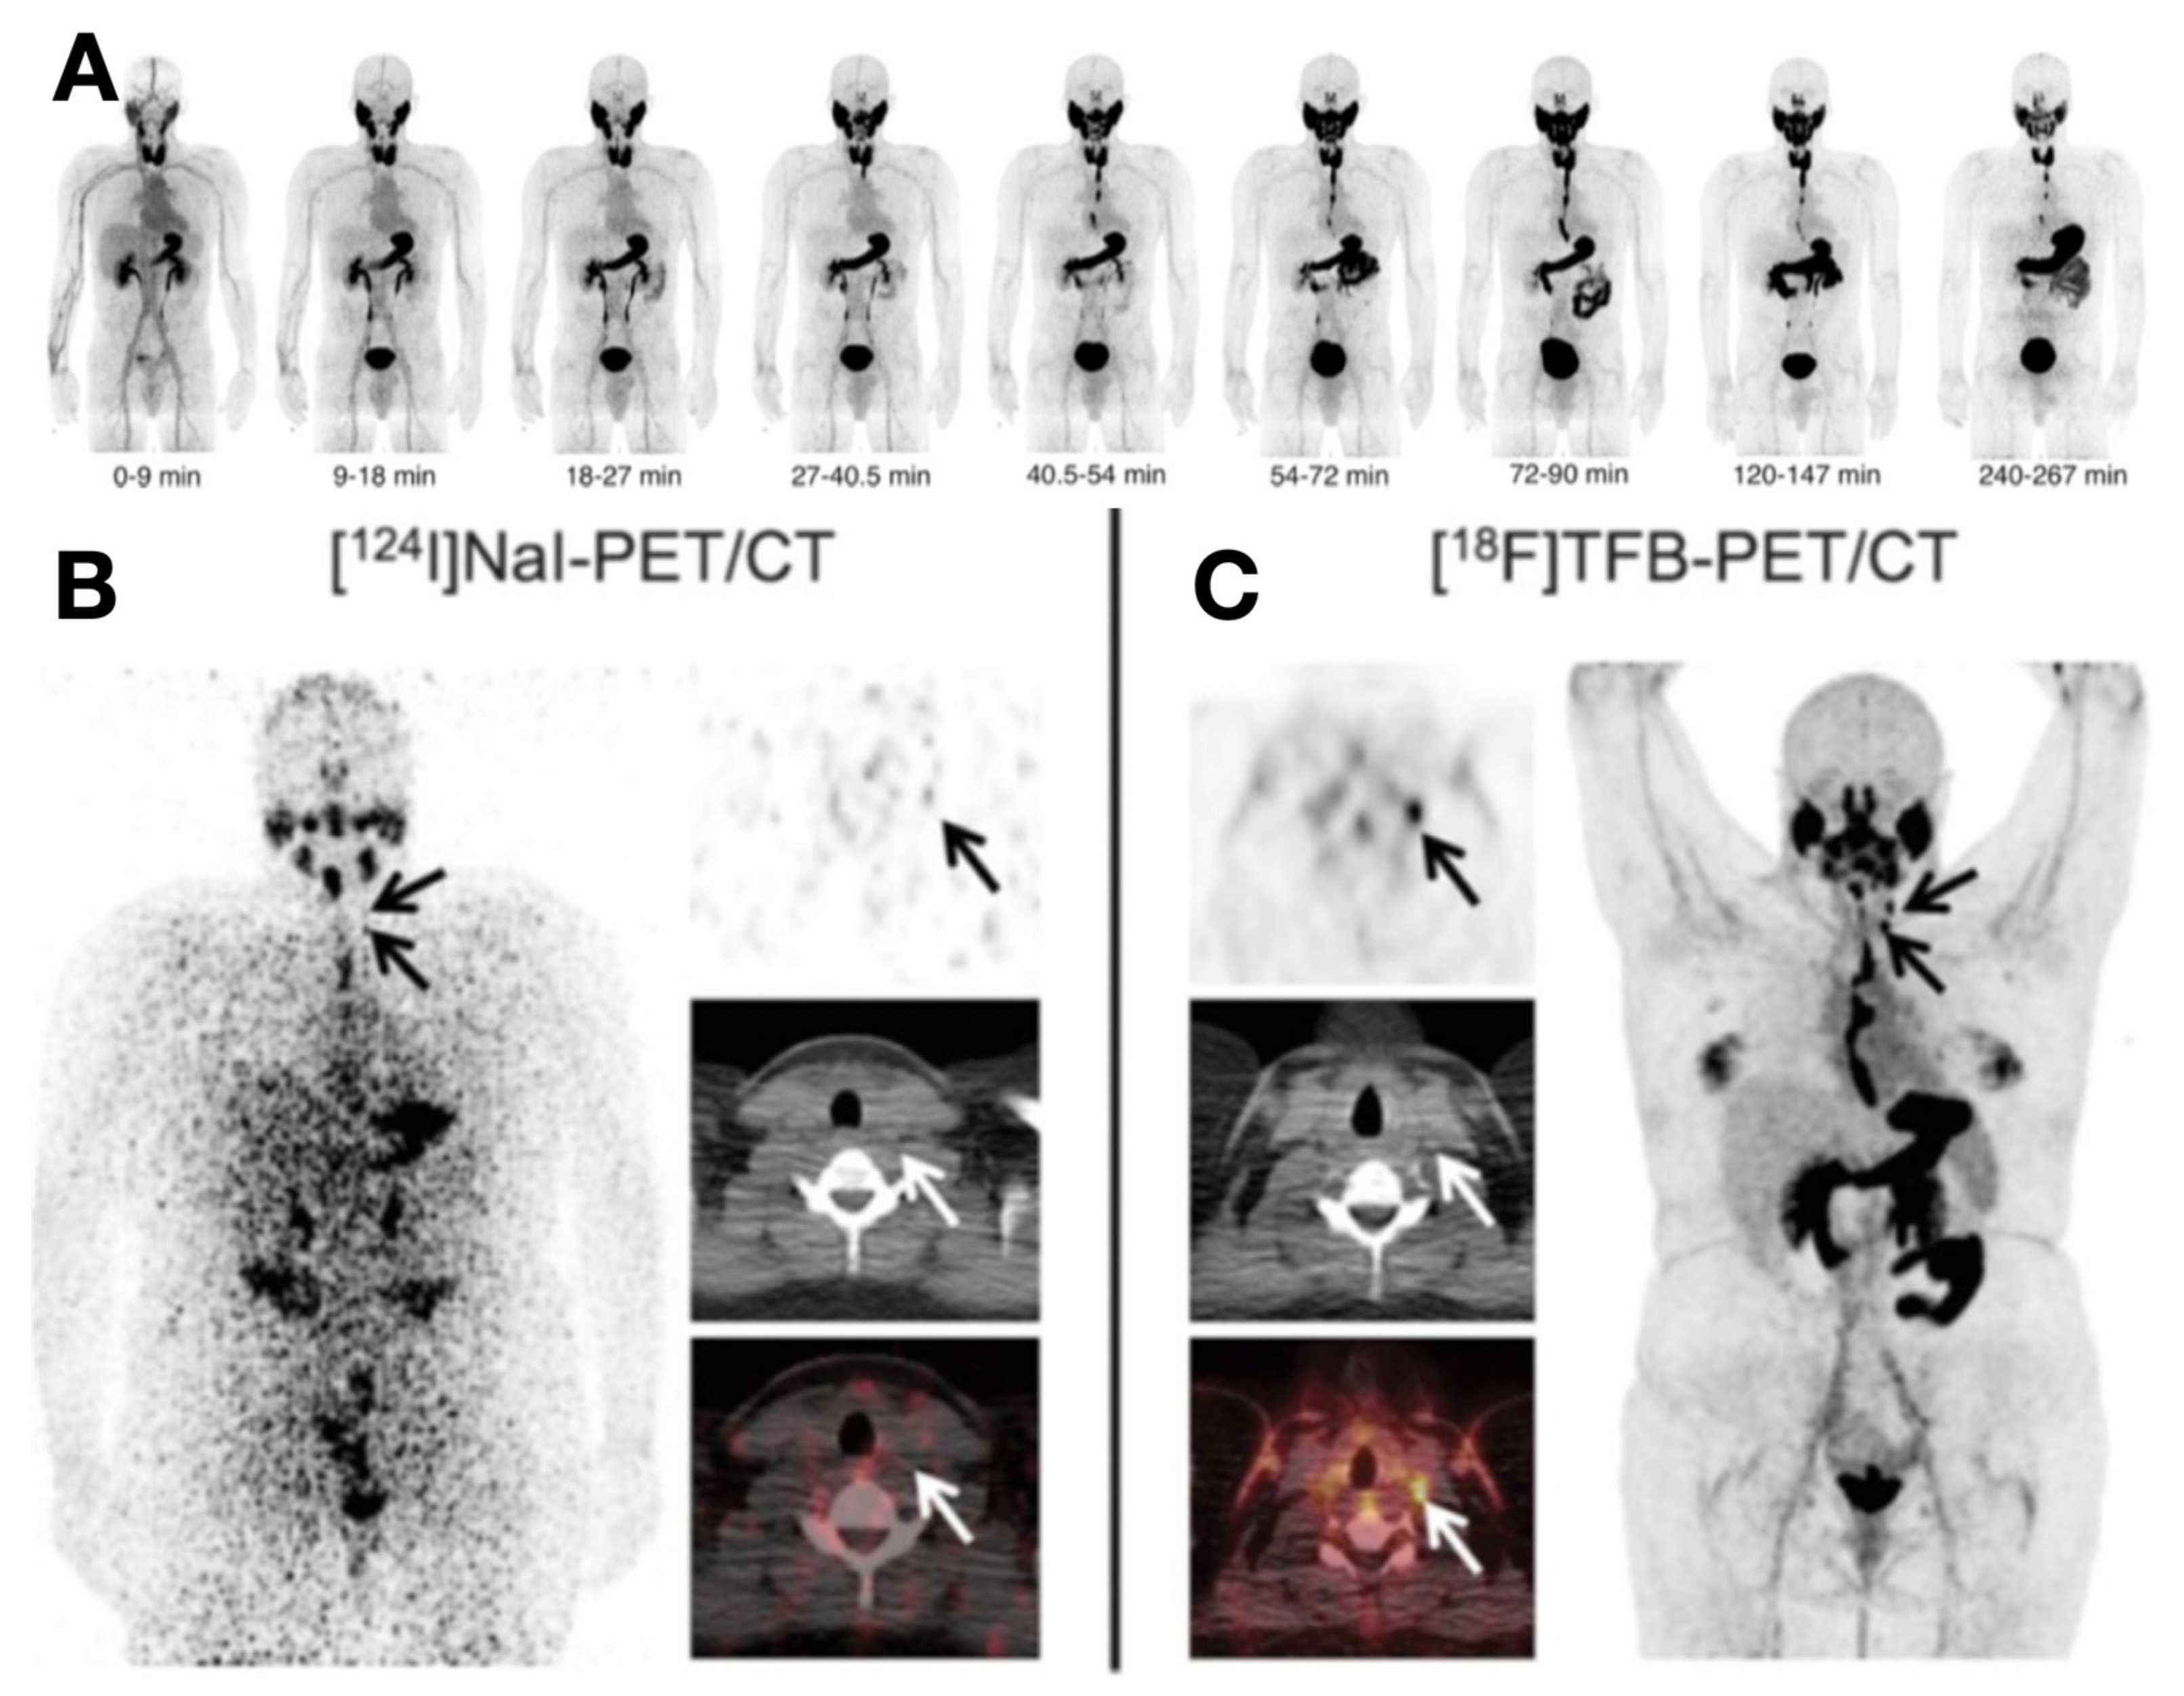

- O’Doherty, J.; Jauregui-Osoro, M.; Brothwood, T.; Szyszko, T.; Marsden, P.K.; O’Doherty, M.J.; Cook, G.J.R.; Blower, P.J.; Lewington, V. 18 F-Tetrafluoroborate, a PET Probe for Imaging Sodium/Iodide Symporter Expression: Whole-Body Biodistribution, Safety, and Radiation Dosimetry in Thyroid Cancer Patients. J. Nucl. Med. 2017, 58, 1666–1671. [Google Scholar] [CrossRef] [Green Version]

- Samnick, S.; Al-Momani, E.; Schmid, J.-S.; Mottok, A.; Buck, A.K.; Lapa, C. Initial Clinical Investigation of [18F]Tetrafluoroborate PET/CT in Comparison to [124I]Iodine PET/CT for Imaging Thyroid Cancer. Clin. Nucl. Med. 2018, 43, 162–167. [Google Scholar] [CrossRef]